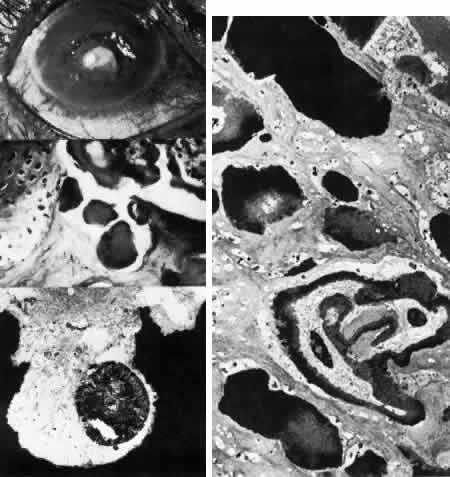

ENDOTHELIAL DYSTROPHIES

Congenital Hereditary Endothelial Dystrophy

Initially described by Maumenee173 in 1960, this congenital disorder of the endothelium is characterized clinically by diffuse, bilaterally symmetric corneal edema (Figs. 5 AND 15; Color Plate 1J). The autosomal recessive variety is present at birth and is relatively stationary. Symptoms of discomfort are not prominent despite profound epithelial and stromal edema. Nystagmus is common.174 A dominantly inherited form is less severe, developing in the first or second year of life, and, in contrast to the recessive variety, progressive photo(text continues on p. 27) phobia and tearing are the initial symptoms. Nystagmus is generally absent.174 As in all instances of congenital corneal clouding, it is important to rule out congenital glaucoma.

Fig. 15. Congenital hereditary endothelial dystrophy. Top left. Clinical photograph of eye of a 14-year-old male with severe form of the dystrophy shows diffuse ground-glass stromal opacification. Top middle. In a mildly affected 20-year-old female, the cornea has moderate diffuse haze and visual acuity is 20/200. Top right. On slit lamp biomicroscopy, diffuse edematous thickening of the corneal stroma is evident in same patient as top middle photograph. Middle right. Light microscopy of a case with uniformly thickened (approximately 35μm) Descemet's membrane (DM) covered posteriorly by extremely attenuated endothelial cells (arrowheads). S, posterior stroma; AC, anterior chamber (hematoxylin-eosin, × 600). Bottom left. Transmission electron micrograph of same case as middle right micrograph reveals anterior portion of Descemet's membrane (DM) to have normal thickness and banded structure. The markedly thickened (approximately 20 μm) posterior layer exhibits both 55 nm and 110 nm banding (circled) interspersed with homogeneous material. En, endothelial cell; AC, anterior chamber; S, posterior stroma (× 9200). Bottom right. At higher magnification, the abnormal posterior zone is seen to consist of multiple laminations of basement membrane-like material (*) and fine filaments. En, endothelial (× 42,000).

The degree of edematous corneal clouding varies from a mild haze to a milky, ground-glass opacification. Epithelial microbullae may be obvious, and stromal thickness may be increased threefold or more. Uniform thickening of Descemet's membrane is sometimes evident on clinical examination, but no guttata are apparent. Interstitial inflammation and secondary vascularization are absent. There are no definitely associated ocular or systemic abnormalities.

Histologic study175–181 reveals nonspecific anterior and stromal changes consistent with long-standing secondary edema: basal epithelial cell swelling, basement membrane thickening and disruptions, and irregularities of Bowman's layer with pannus formation. However, it may be significant that, in some cases, ultrastructural examination discloses greatly enlarged stromal collagen fibrils sometimes measuring as much as 60 nm in diameter. Descemet's membrane is uniform in a given specimen; it may display diffuse thinning of 3μm to massive thickening of 40 μm (normal thickness is 3 to 5 μm in neonates and 8 to 10 μm in adults). The anterior banded layer of Descemets membrane is always present and of relatively usual thickness; however, the posterior layer consists of multilaminar basement membrane-like material with fine filaments and of collagen fibrils with a 55- and 110-nm banded configuration. With the exception of the lack of guttata, these findings are similar to those in Fuchs' dystrophy and thus represent another example of posterior collagen layer formation by either primarily or secondarily abnormal endothelium.18,41,43,181, It is postulated that in cases with thin Descemet's membrane, complete endothelial loss occurred in utero such that only the fetal anterior portion of Descemet's membrane was secreted.180 In contrast, cases exhibiting thickened Descemet's membranes may be the product of dystrophic but persistent endothelium having secreted a hypertrophic posterior collagen layer.

The frequent finding of enlarged stromal collagen fibrils suggests some primary developmental abnormality of both keratocytes and endothelium, thus perhaps qualifying this disorder as another example of mesenchymal dysgenesis.22